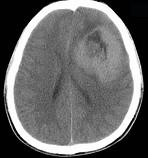

男,15岁,进行性头痛1年余,CT检查如图所示,最可能的诊断为()A.脑膜瘤B.脑血管畸形C.转移瘤D.淋巴瘤E.胶质母细胞瘤

问题 男,15岁,进行性头痛1年余,CT检查如图所示,最可能的诊断为()

选项 A.脑膜瘤 B.脑血管畸形 C.转移瘤 D.淋巴瘤 E.胶质母细胞瘤

答案 E